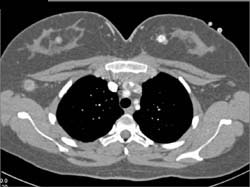

Lung Cancer Metastatic to Subcutaneous Tissue